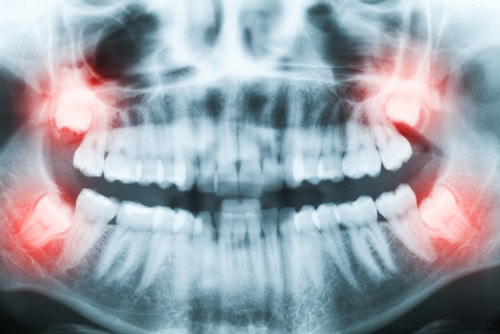

Let’s start with the basics. Wisdom teeth, or third molars, are a set of molars in the very back of the mouth. There are a total of four wisdom teeth, one in each quadrant of the mouth. They are also the last set of teeth to emerge. In fact, they usually do not emerge until 5 to 10 years after the rest of the permanent teeth emerge.

By the time they emerge, the patient already has a full set of functional teeth. Since wisdom teeth are also the largest teeth in the mouth, there is not always enough room inside the jaw for them. In other cases, there may be enough room, but they are growing in sideways rather than vertically, pushing against the second molars as they come through (more on this below).

- Impacted teeth

Wisdom teeth that grow sideways or emerge when there is not enough space in the jaw can damage other teeth and gums. It can also make orthodontic treatment more challenging, which is why dentists typically recommend wisdom tooth extraction before orthodontic care.